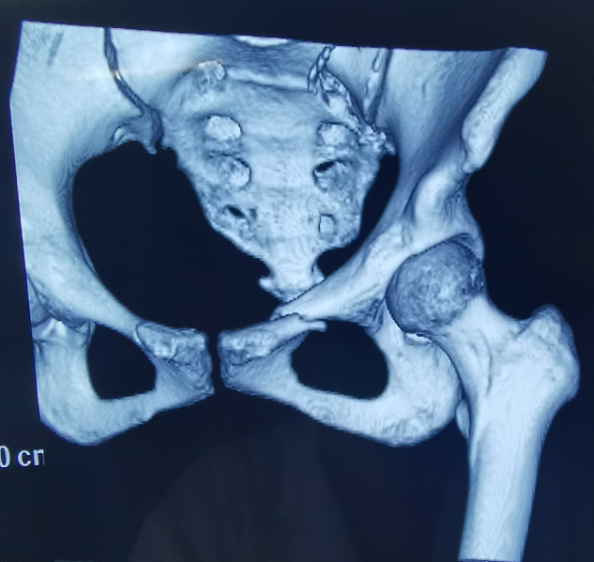

患者为22岁年轻女性,,,,,因车祸致骨盆骨折。。。。。。骨盆骨折是一种重大的创伤,,,,,古板手术方法需要较量大的切口,,,,,并且骨盆内有大宗重大血管和神经,,,,,手术难度和危害极大,,,,,是许多骨科医生的禁区。。。。。。

在古板骨科手术中,,,,,重复使用X线透视,,,,,有时须经常调解或更改手术牢靠方法,,,,,经常需要多年的临床履历积累,,,,,也难免意外频发,,,,,事实人眼判断和X线透视单平面视察的局限性是客观缘故原由。。。。。。